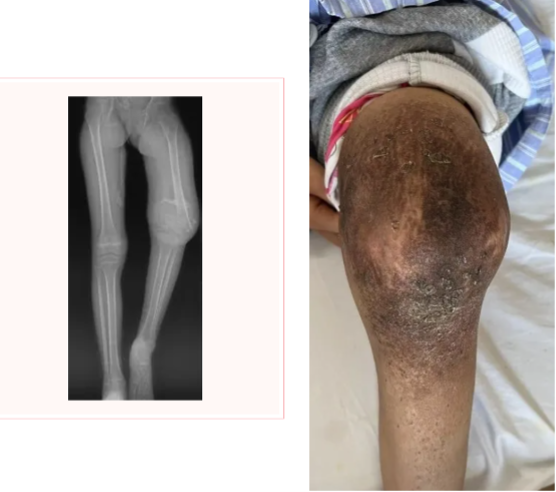

图示:患者左侧股骨远端骨肉瘤伴病理性骨折,就诊时膝关节肿胀明显伴有畸形

由于已经出现了病理性骨折,周围软组织肿瘤累及范围较大,对保留血管及神经功能要求高。当地建议行截肢手术治疗。